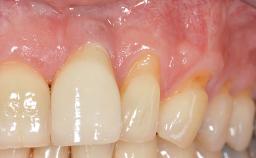

GBR and Soft-Tissue Augmentation Following Explantation to Rehabilitate a Soft- and Hard-Tissue Defect

It is sometimes necessary to remove and replace compromised implants. This case is a clear example of the need for multiple steps to achieve an optimal therapeutic result for patients with non-salvageable implants. It illustrates how the lost soft and hard tissues were rebuilt in a sequence that improved the healing of the hard tissues and assured their long-term stability. The 35-year-old healthy patient presented with clinical attachment loss on the proximal and lingual surfaces of the natural dentition. Some gingival recession was present on natural teeth, particularly in the posterior sextants (S1, S3, S4, and S6).

Soft Tissue Anatomy Intact Defective

Bone Volume Horizontally and vertically sufficient Horizontally deficient Deficient vertically or deficient vertically AND horizontally